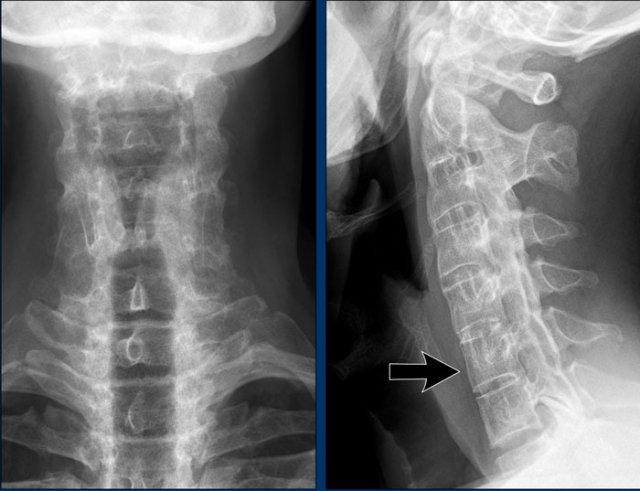

Trật khớp đội – trục

Cột sống cổ thường bị ảnh hưởng trong viêm khớp dạng thấp và có thể biểu hiện dưới dạng mất vững khớp đội – trục, trật khớp dưới trục hoặc lồng nền sọ kèm theo sụt lún sọ não.

Sụt lún sọ não xảy ra khi mỏm răng xâm lấn vào lỗ chẩm.

Trật khớp đội – trục là một biến chứng quan trọng và có thể đe dọa tính mạng của viêm khớp dạng thấp. Tình trạng này được xác định khi khoảng cách giữa mỏm răng C2 và cung đốt đội vượt quá 3 mm. Nguyên nhân là do lỏng lẻo dây chằng do viêm.

Mất vững tại khớp này có thể gây ra nhiều triệu chứng thần kinh do chèn ép tủy sống.

Hình ảnh

Khi cúi cổ, khoảng cách giữa mỏm răng và mặt sau cung trước đốt đội bị giãn rộng (14 mm) (bình thường ≤3 mm).